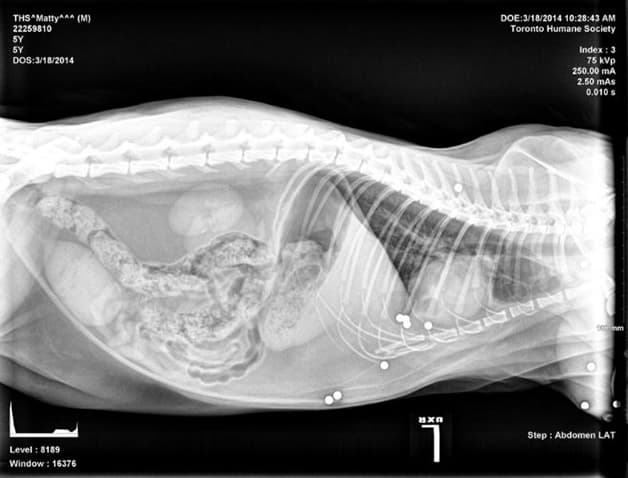

Chụp X quang khi mang thai tiềm ẩn nguy cơ gây dị tật thai nhi

Chụp X quang trong giai đoạn mang thai 4 tuần tiềm ẩn nhiều nguy cơ gây hại cho thai nhi